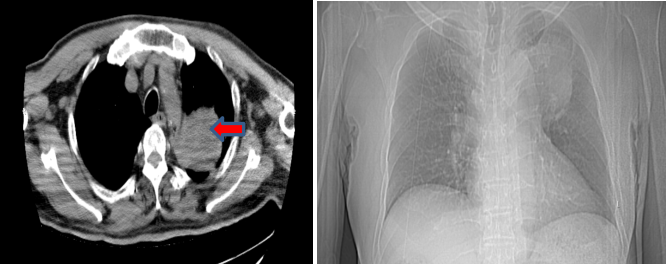

胸部CT(2023年10月):左肺上叶占位较前增大,疗效评价为疾病进展(PD)。此时,患者已获得约12个月的无进展生存期。

4.png

胸部CT(左:2023年4月;右:2023年10月)

后续治疗

针对胸部病灶的进展,患者于2023年11月10日开始接受胸部姑息性放疗,放疗总剂量为:PTV 5500cGy,共25次,每次220cGy,放疗期间患者暂停用舒格利单抗。放疗结束后,于2024年1月29日继续重启舒格利单抗维持治疗。截至目前,患者已接受共计31个周期的舒格利单抗维持治疗,并仍在持续治疗中。